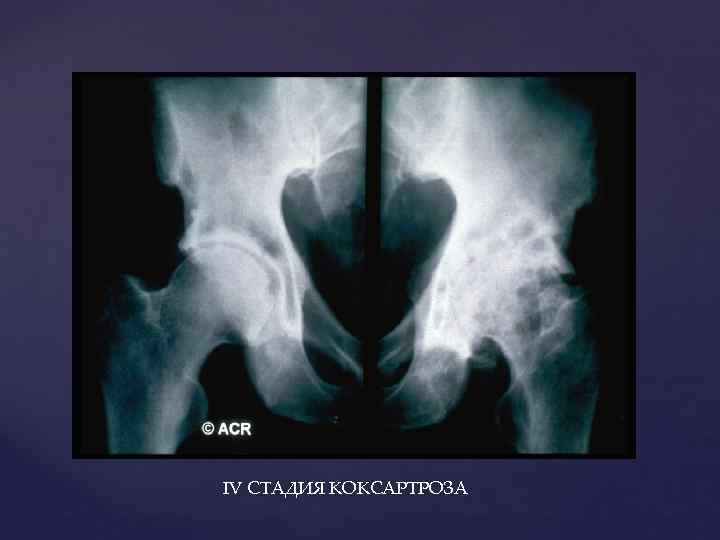

IV СТАДИЯ КОКСАРТРОЗА

IV СТАДИЯ КОКСАРТРОЗА